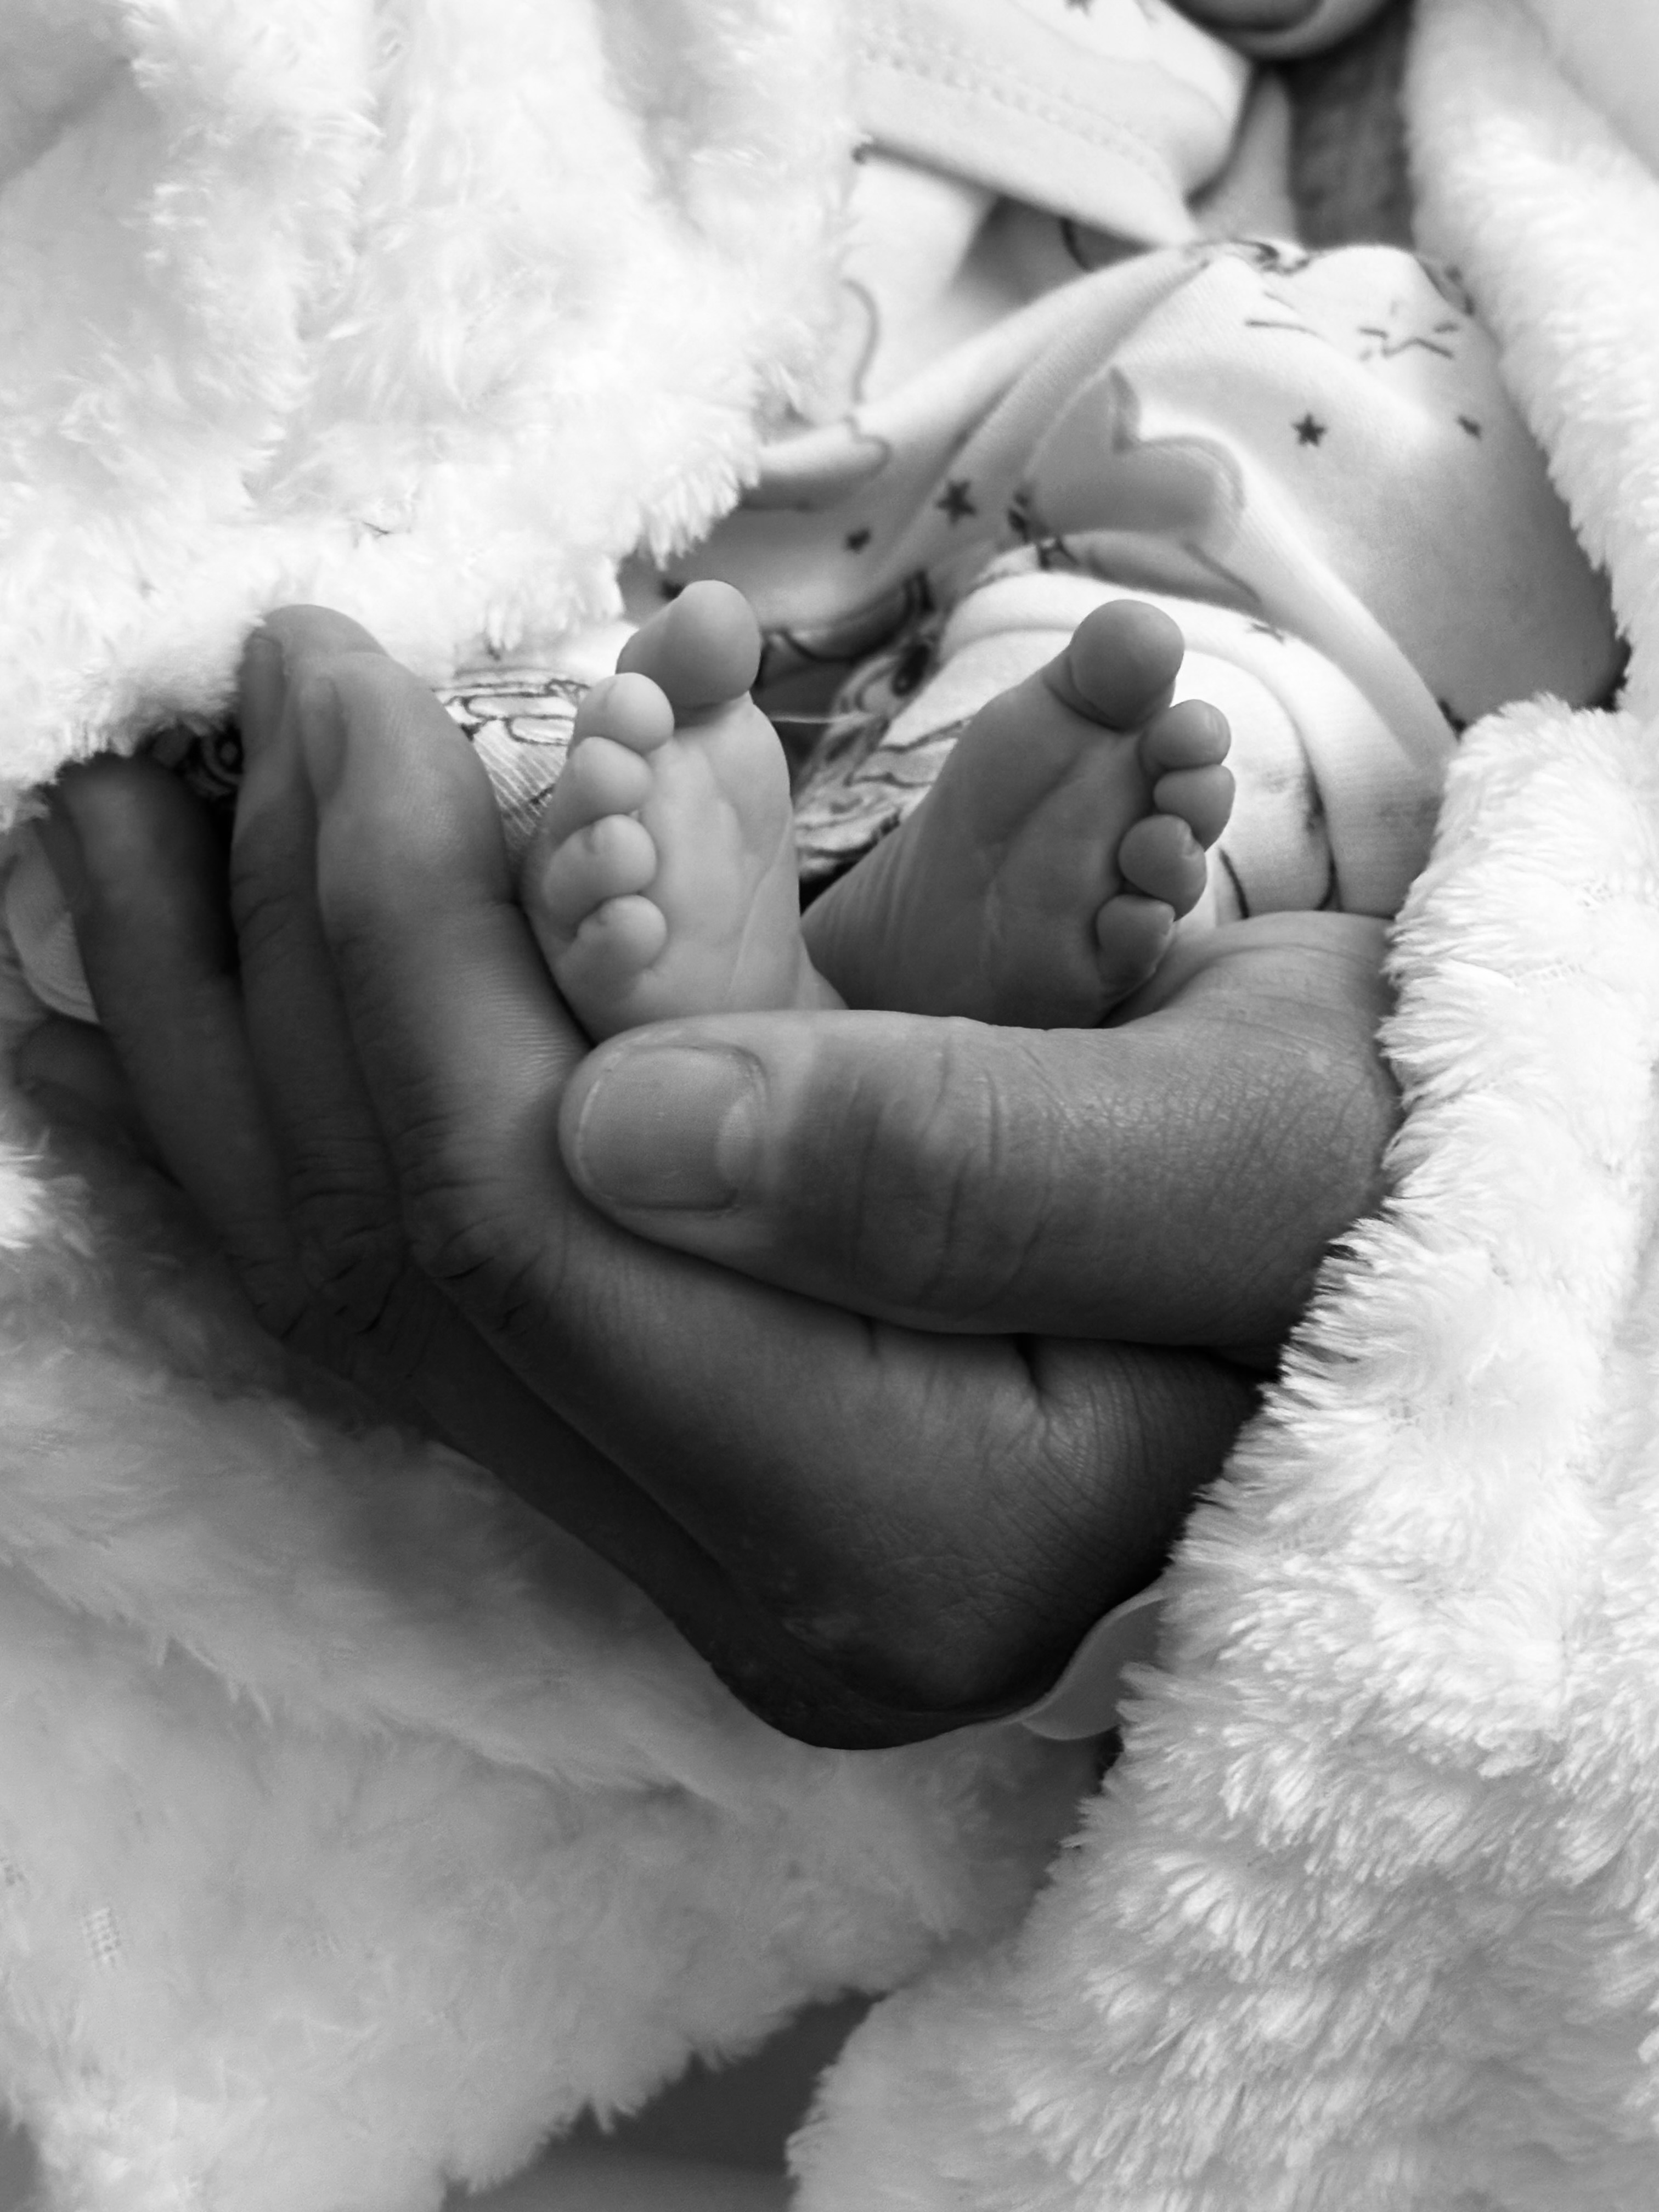

DeAngelo Has passed Away Sep 15 2025 @ 9am.

On July 25th, 2025 we got devastating news that DeAngelo has a rare condition called CDH with a broken heart im here to ask for prayers for baby DeAngelo . We had got news about a month ago that his health wasn’t so good but with faith we continued to look forward for getting him surgery. The first clinic failed the family in telling them the baby was completely healthy. If it wasn’t for the mother wanting to change clinics and hospitals for delivery they wouldn’t have did further test for the baby in which we found out at 37 weeks he was diagnosed with a syndrome called CDLS Adding the syndrome on top of the issues he has going on we don’t know what’s going to happen to him. C section is scheduled for Monday sep 15 @ 8am. Isha is already in the hospital with high blood pressure & will be delivering the baby early @ 37 weeks & you know with that she will be needing a lot of help from Andrew who will be missing work to stay by her and the baby’s side . We don’t know if he’ll survive the intubation or if he will be born still at birth . We ask from the bottom of our hearts to help with whatever you can in case baby DeAngelo has to be put to rest . God bless.